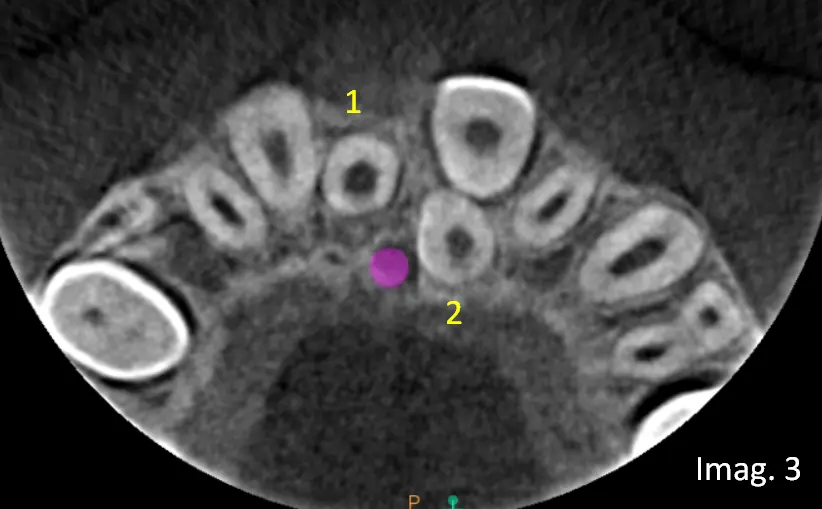

En el estudio tridimensional se confirma la presencia del Mesiodens clínicamente observable y además se identifica un segundo Mesiodens incluido, no detectable en el estudio panorámico inicial (ver imagen 3, vista axial).